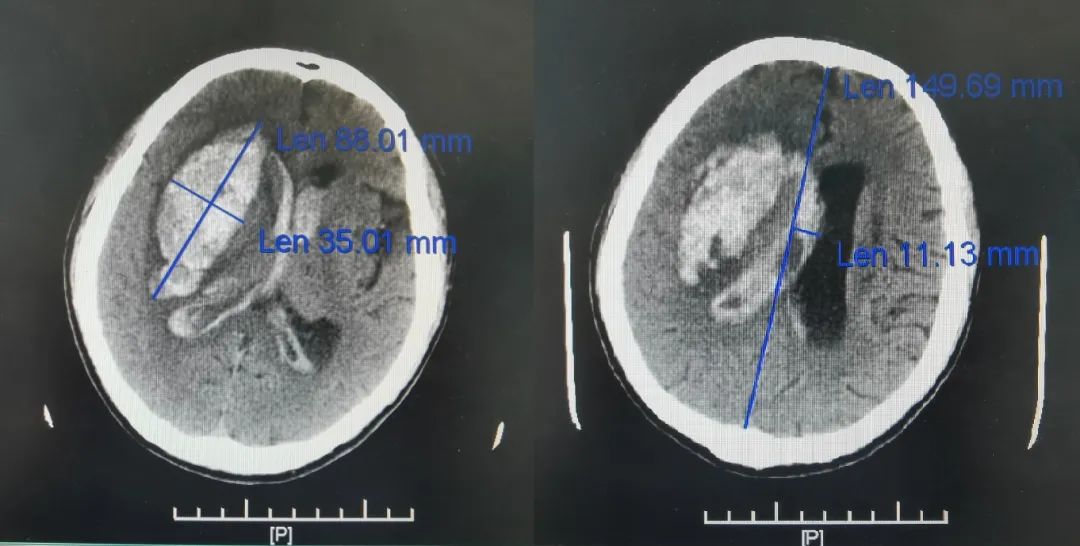

神经疾病诊疗中心张滨海副主任医师阅片后考虑患者脑出血破入脑室,因发病时间短、出血量巨大、到院后进行性意识障碍加重,影像学提示中线移位明显,为极危重脑出血患者,存在急诊手术指征,建议立即开颅手术治疗。

病人在急诊完成术前准备后立即送入手术室。手术的同时,重症医学科紧锣密鼓的调整床位,做好术后接诊准备。5月9日凌晨1点手术顺利结束,病人安返重症监护室。目前复查头CT显示血肿已彻底清除,患者基本情况稳定。